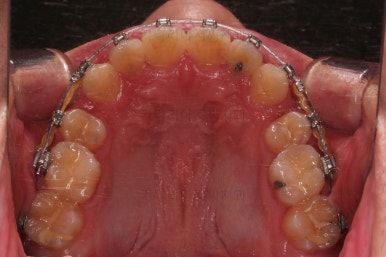

초진 시, 입안의 모습입니다.

치아를 모두 담기에 골격이 매우 작았어요.

이런 경우 치열이 ㅃ뚤어지거나 입이 튀어나오거나 뻐드렁니가 되거나 특정 치아가 묻혀버리거나 맨 뒤치아가 마치 사랑니처럼 올라오지 못한다거나 등등의 문제가 생기는데요.

이번 환자분은 전반적으로 삐뚠 상황이었어요.

앞니도 대칭적으로 삐뚤어져 흔히 나비치아라고 하는 형태로 보이고, 아랫니들은 U자 아치의 형태가 찌그러져 있네요.

당연히 교합도 맞지 않고요.